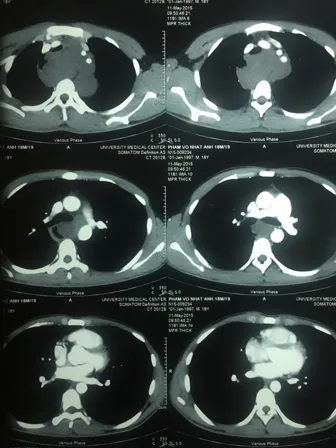

Chụp CT- Scan phát hiện bệnh nhân có khối u lớn ở vùng trung thất.

Trước đó, bệnh nhân P. V. N. A., (sinh năm 1997, ở Cần Giờ, TP.HCM) đến khám tại bệnh viện vì có cảm giác vướng khi nuốt và khó thở khi nằm. Tình trạng này kéo dài gần một tháng và bệnh nhân đã đi khám ở nhiều bệnh viện nhưng không tìm ra bệnh. Qua thăm khám, các bác sĩ phát hiện bệnh nhân có khối u lớn ở vùng trung thất gây chèn ép vào đường ăn và đường thở. Bệnh nhân được sinh thiết, kết quả cho thấy bệnh nhân bị u sợi thần kinh khổng lồ chiếm toàn bộ vùng cổ và trung thất sau. Khối u bao quanh các mạch máu lớn vùng trung thất và dính với thực quản.